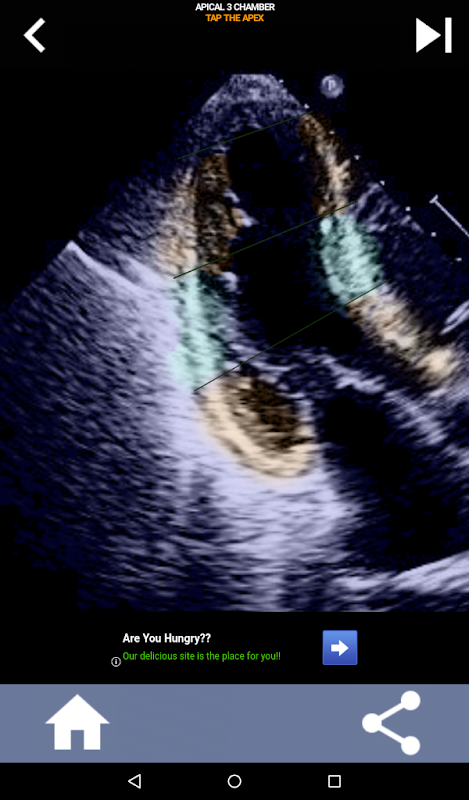

AHA 심장 세그먼트 학습을 위한 퀴즈 기반의 시각적 접근 방식: 심초음파

AHA(미국 심장 협회) 심장 세그먼트를 이해하는 것은 심장 초음파 기사가 보고서를 작성하는 심장 전문의와 효과적으로 의사 소통하는 데 가장 중요합니다. 특정 해부학적 부위와 해당 부분을 알면 소노그래퍼는 모든 이상 또는 발견 사항을 정확하게 설명하고 전달할 수 있으므로 두 전문가 간의 명확하고 간결한 커뮤니케이션이 보장됩니다.

이 앱은 실제 에코 이미지를 사용하여 여러분의 지식을 테스트할 것입니다. 저는 종종 이것이 최고의 교육 방법이라고 생각합니다.